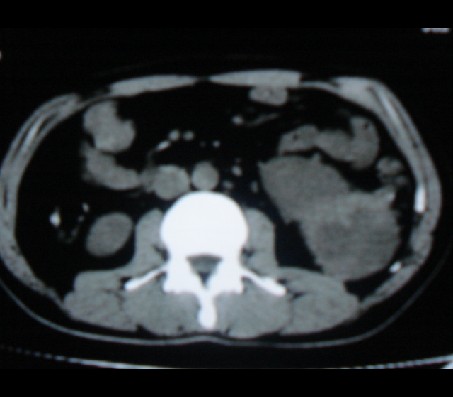

标题: CT20935:左肾占位,请会诊!

男性,35岁,ct号26189,左侧腰痛并血尿一天入院。

左肾癌侵犯肾盂可能性大,建议增强.

考虑左肾癌可能性大,建议增强扫描。

左肾癌侵犯肾盂可能性大。

肾癌侵犯肾盂,肾盂出血,肾盂内为血肿

首先考虑恶性肿瘤性病变,考虑左肾癌可能性大,建议增强扫描。